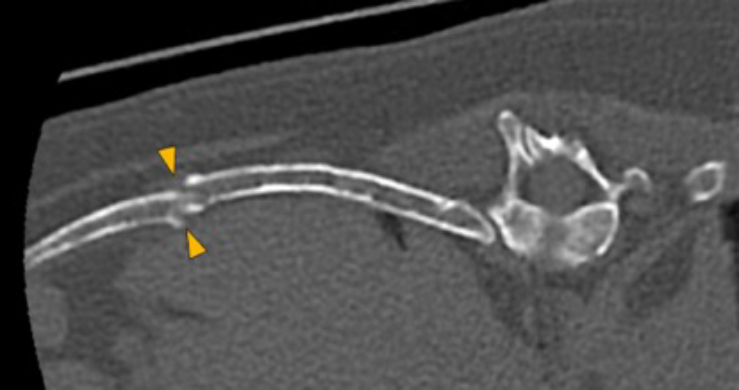

The osteolytic lesions have soft tissue attenuation that shows moderate and slightly heterogeneous post-contrast enhancement. In some of the vertebrae, the lesions cause lysis of the cortex and extend into the vertebral canal (orange arrows) causing variable degree of compression of the spinal cord and cauda equina (blue arrows). At the level of the vertebral bodies of T7, T8, T9 and T12 the lesions extend into the ventral and central aspect of the vertebral canal causing a mild compression of the spinal cord. At the level of T13, L1, L4 and L5 the lesions extend into the ventral and central aspect of the vertebral canal, causing moderate compression of the spinal cord. At the vertebral body of L6 the lesion extends into the ventral and central aspect of the vertebral canal, at the mid-aspect of L6, occupying approx. 90% of the diameter of the vertebral canal causing a severe compression of the cauda equina. At the level of L7, the lesion extends into the ventral and both lateral aspects of the vertebral canal, causing severe compression of the cauda equina.

There are multiple osteolytic lesions with the same characteristics affecting both scapula and the pelvic bones included (pink and blue arrows respectively). There are osteolytic lesions with the same characteristics affecting multiple ribs. Associated with these lesions, there are multiple rib fractures.

Dog, thoracolumbar spine, ribs